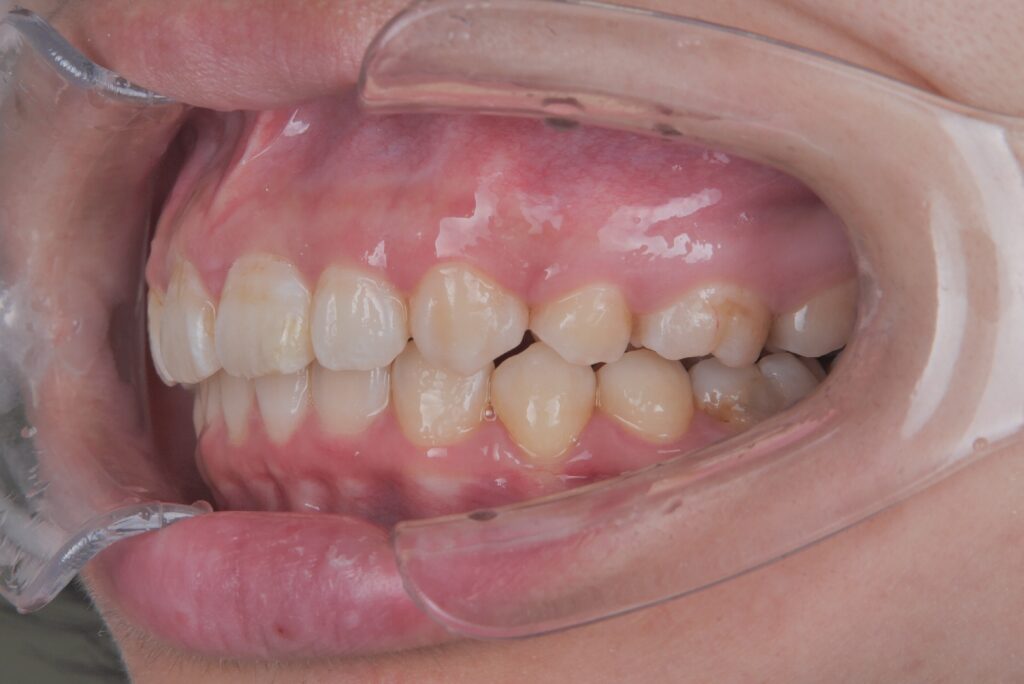

例えばこのケースは、重度のガタガタで、通常であれば抜歯矯正を選択したいケースでしたが、横顔がきれいなEラインであったので、これ以上下げると、若い時はいいのですが、お年を召されて、ほうれい線がめだったり、よく巷で言われる老人様顔貌になることが予測されたため、3次元のCT写真で正確に診断し、非抜歯で仕上げたケースになります。

重度のガタガタでしたが、抜歯矯正でなく、非抜歯矯正で治療することで、歯並びはもちろんのこときれいな横顔のまま、今日治療を終了することができたケースになります。